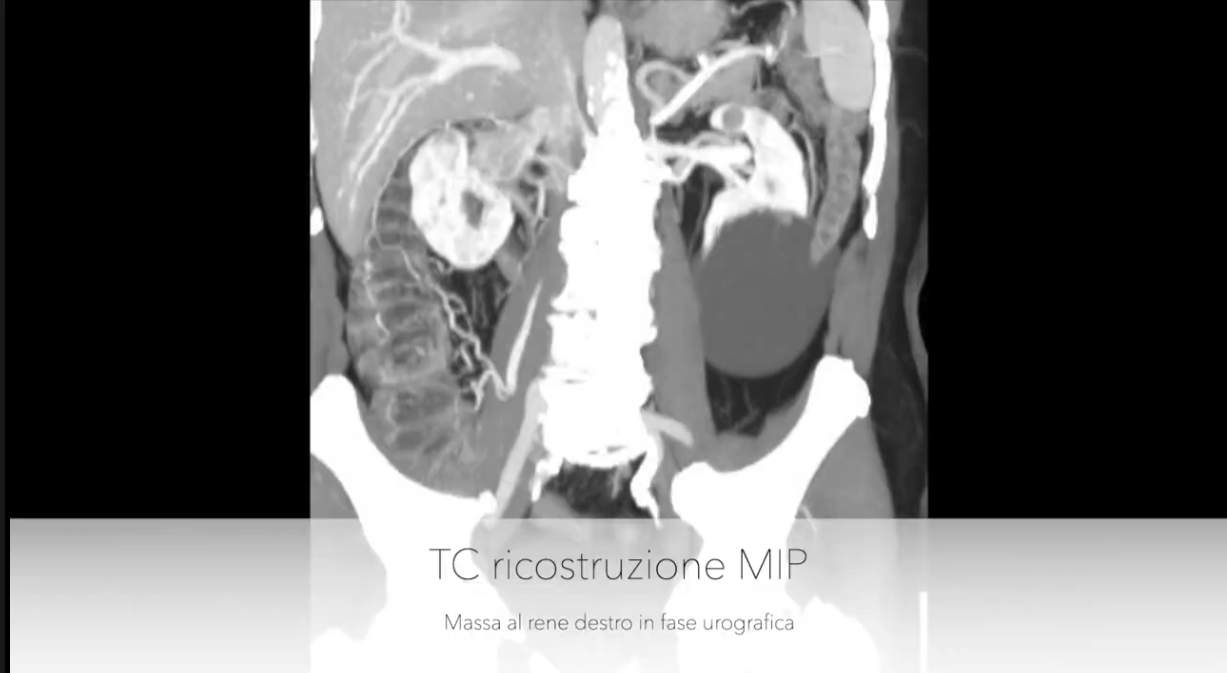

Nefrectomia radicale destra con trombectomia cavale laparoscopica 3D